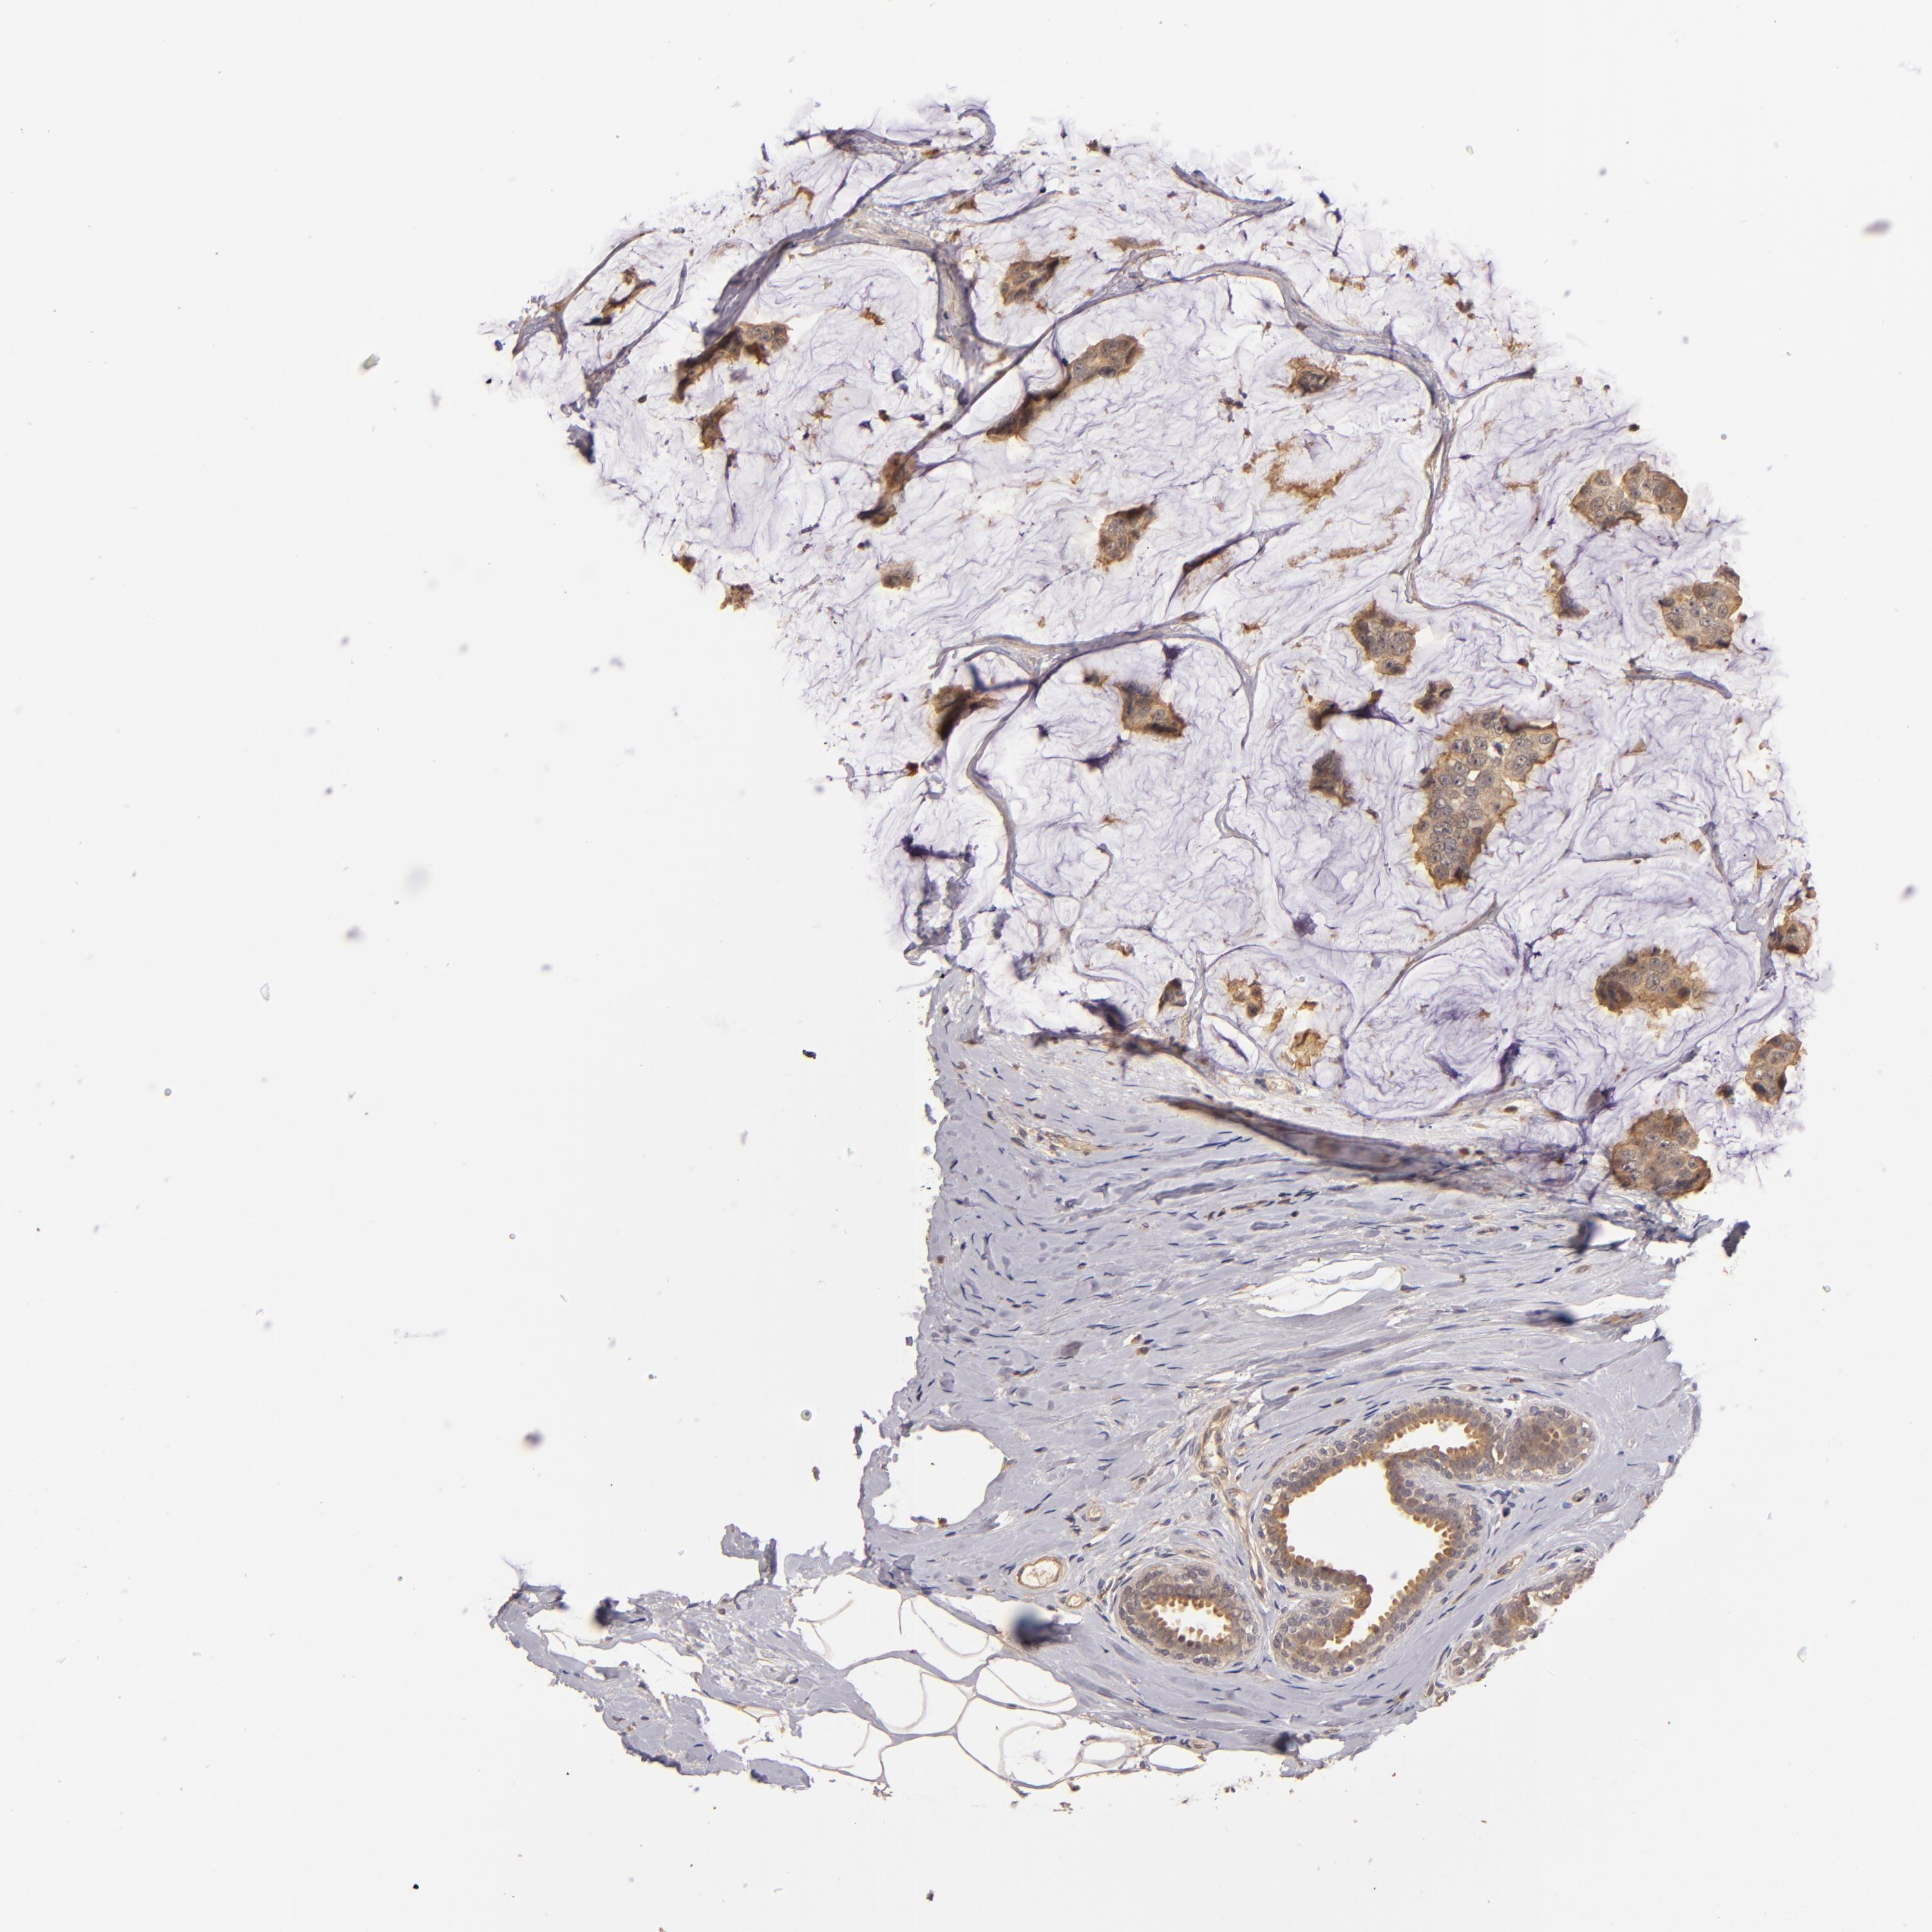

BRCA TCGA BRCA VALIDATION PROTEIN EXPRESSION